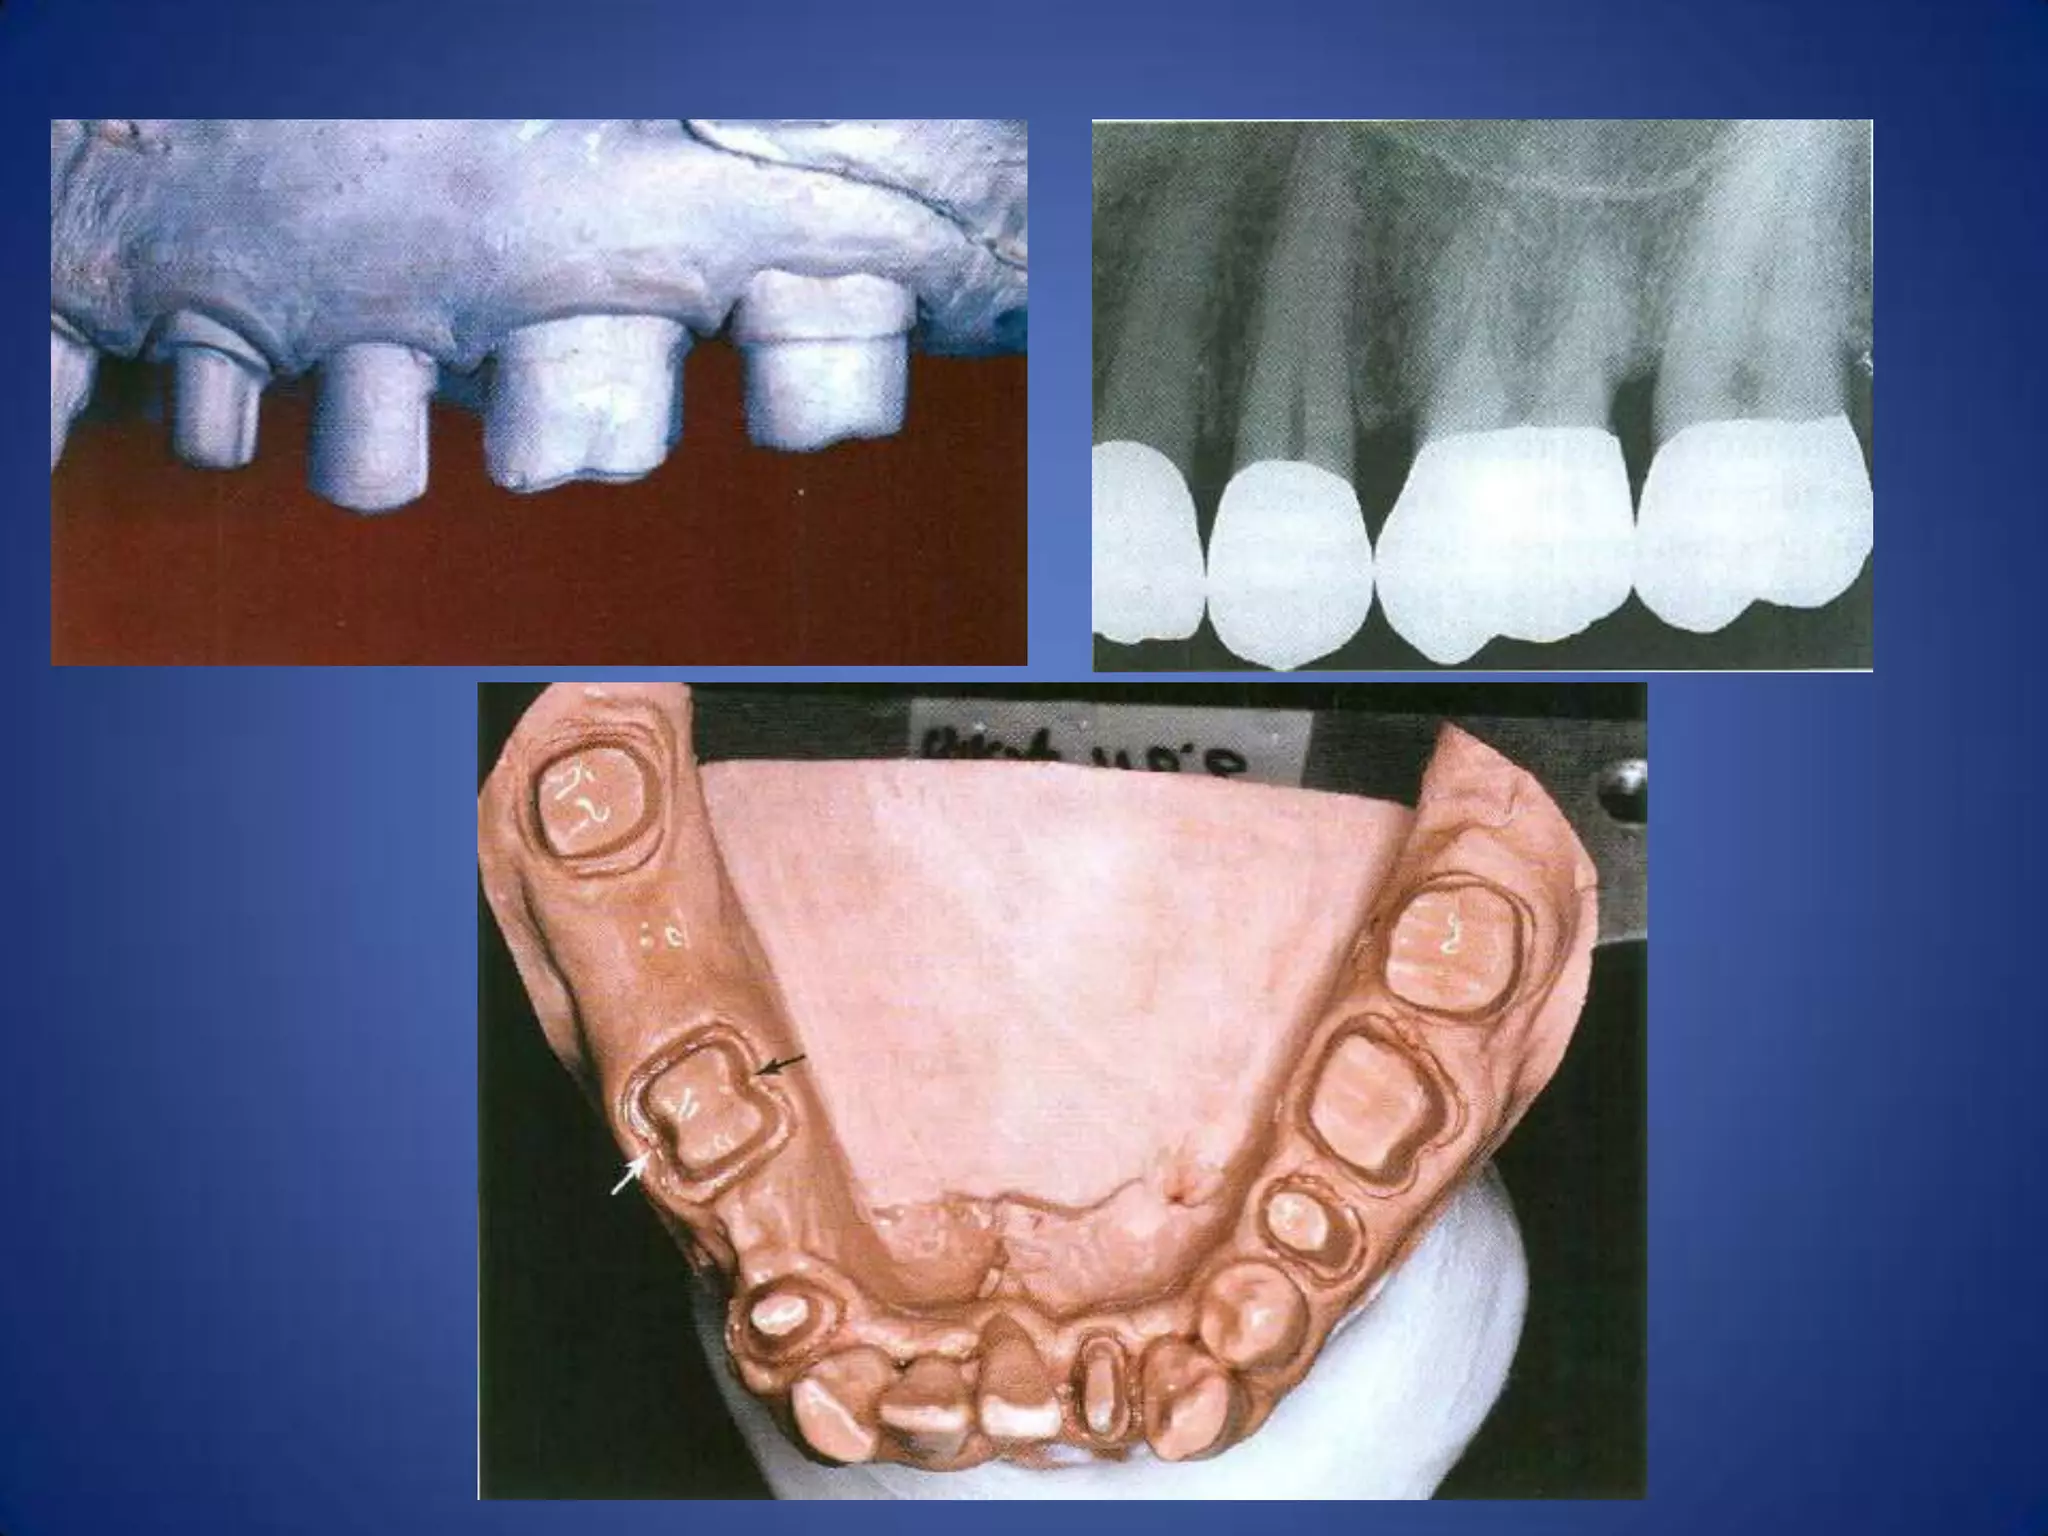

Margin placement

Whenever possible, the margin of preparation

should be supragingivally, where the supragingival

margin is prepared on sound enamel, while the

subgingival margin is often prepared on cementum

advantages:

1- Easier to prepare accurately without trauma to

soft tissue.

2- Prepared on hard enamel.

3- Easy to finished.

4- More easily to kept clean.

5- Impression are more easily made.

6- Restoration can be easily to evaluated at recall

appointment.

Indications of subgingival finish line

1- Dental caries, cervical erosion, restoration extend

subgingivally.

2- Proximal contact area extend near gingival crest.

3- Short tooth and additional retention is required.

4- The margin of metal-ceramic restoration is to be

hidden subgingivally.

5- Root sensitivity cannot be controlled by

conservative procedures.

Marginal Geometry

Ideal requirements of finish lines:

1.

They must fit closely to the finish line of the

preparation.

2.

They must have sufficient strength to

withstand the force of mastication.

3. Whenever possible, finish line should be

located in areas where the dentist can finish

and inspect them, and the patient can clean

them